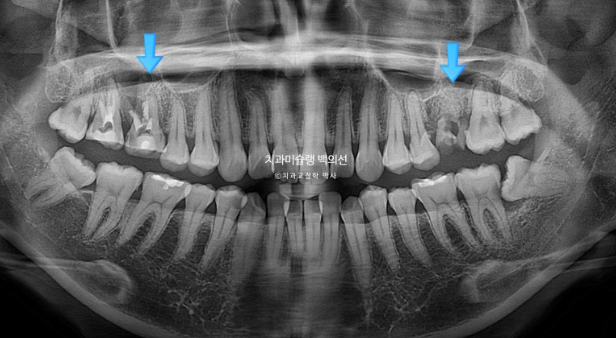

파란화살표 둘째 큰어금니 (제2대구치)자리에 있는 치아는 사실 사랑니입니다.

그 앞 제 1대구치 자리에 와있는 치아는 사실은 제 2대구치입니다.

쓰러짐 없이 잘 배열되었으며 치근평행도는 좋습니다.

치근흡수는 없습니다.

인비절라인 교정에서 치근흡수는 체감상 클리피씨 교정의 1/10도 안되는 것 같습니다.